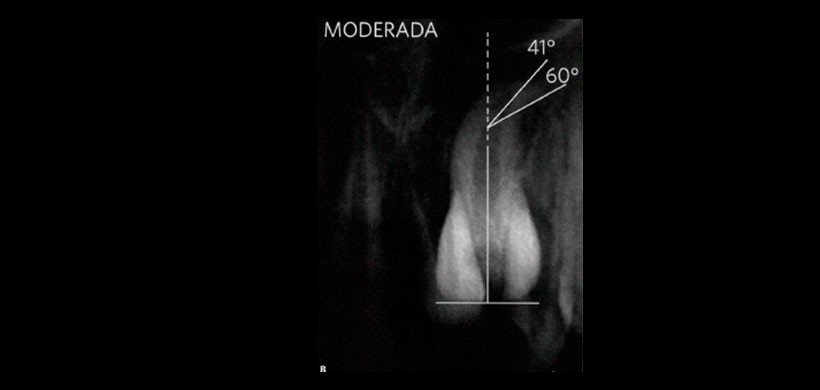

Fig 2. Dilaceración radicular tipo MODERADA, se considera una angulación de hasta 60°.